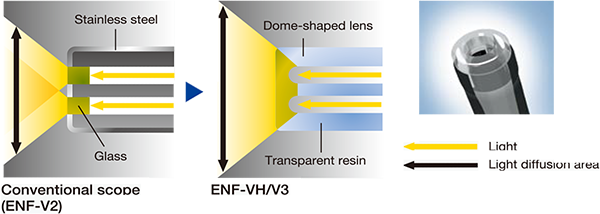

Exceptional luminosity

Although it has a small diameter, the scope still illuminates abroad area, providing a detailed image of any lesions withinthe field of view. This exceptional luminosity is especialyuseful when observing with NBl.